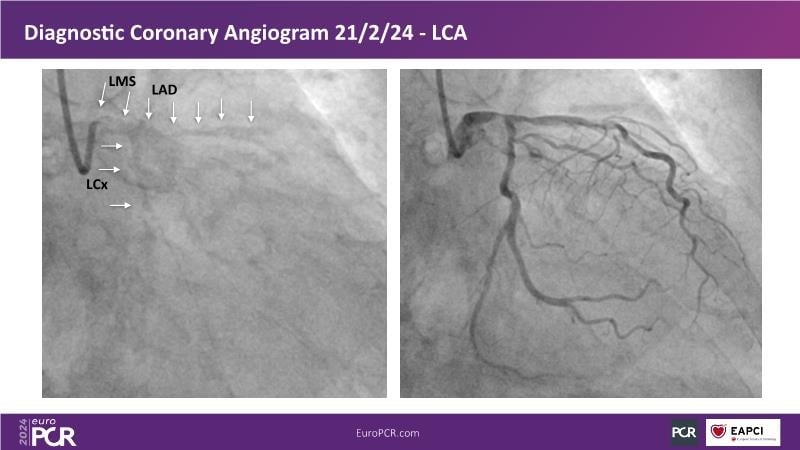

From innovation to reality: the impact of Cre8 EVO technology on complex PCI

This session is a good opportunity to delve into the contemporary technical and clinical complexities surrounding complex PCIs in challenging patient cases. Explore the necessary tools and treatment strategies to enhance peri-procedural and long-term clinical outcomes, and follow discussions on the unique technologies of Cre8 EVO in complex PCI scenarios.